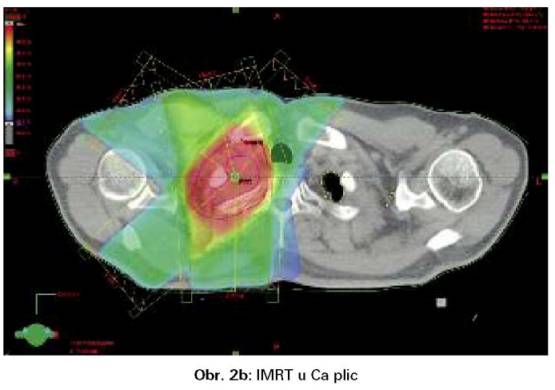

Významným zlepšením přesnosti ozáření se stala radioterapie s modulovanou intenzitou (IMRT). IMRT rozkládá svazek záření na jednotlivé paprsky s proměnlivou intenzitou. Výsledkem je programové kolísání fluence záření napříč ozařovacím polem a zpřesnění ozáření i velmi nepravidelných cílových objemů. IMRT může zlepšit pokrytí cílového objemu a redukovat dávku na plíce (obr. 2a,b). Indikací jsou zejména nádory v těsné blízkosti jícnu a míchy (6,7).